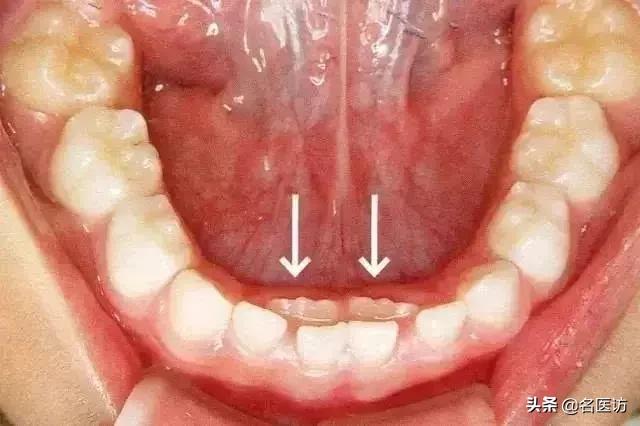

孩子这是乳牙还没脱落,新牙就长出来了,表现为”双排牙“现象。这种情况就是我们所说的“乳牙滞留”。

1、 继承恒牙已萌出,而乳牙未脱落,称早期滞留;

2、恒牙未萌出,但已超正常换牙年龄极限仍未脱落的乳牙,称晚期滞留;

乳牙滞留的原因有很多,比较常见的原因是现在的小朋友饮食过于精细,牙弓长度发育不足,继承恒牙没地儿长造成萌出方向异常,乳牙牙根吸收不完全,所以不能自行脱落。

遇到乳牙滞留形成的“双排牙”,家长应该尽快带孩子到牙科医院拔除滞留乳牙,为恒牙的发育腾出空间让出位置。

对恒牙已萌出而乳牙仍未脱落的滞留牙,应尽快拔除,以免影响恒牙在正常位置上萌出。

但是超过换牙年龄而乳牙未脱落,恒牙又未萌出者,则不要轻易拔掉,若是恒牙先天性缺失,应尽量保持乳牙。